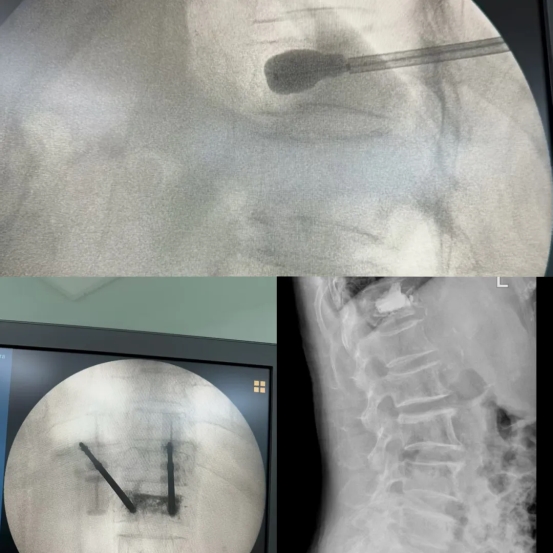

手术过程中,医生在患者皮肤上仅开一个约 0.5cm 的微小切口随后,特制的球囊通过导管被小心翼翼地送进骨折的椎体内,慢慢撑开球囊,为受损的椎体创造修复空间。接着,注入骨水泥填充骨不愈合或坏死处,加固椎体,为脆弱的骨骼筑起坚固的“防线”。

这场手术在不到 20 分钟的时间里就顺利结束。术后仅 1 天,李奶奶在佩戴腰围的辅助下,就能稳稳地下地行走。她和家人对治疗效果赞不绝口,对脊柱外科团队的精湛医术和贴心关怀感激不已。